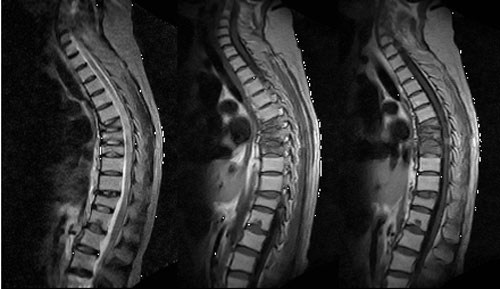

女性 45岁 患肾病综合症1年 有长期使用激素史 现诉背部疼痛。

椎弓根无破坏,椎间隙正常存在,椎旁未见软组织肿块,结核及转移可见除外吧,考虑压缩性骨折

骨质疏松所致的压缩性骨折

上不着村下不着店,胸骨也未见到,很难定位。结合病史考虑为骨质疏松所致多发性胸椎骨折合并节段性胸髓损伤。

检查技术有待改进,自己给自己出了一个无法解决的难题,定位?暂时考虑单纯多发压缩性骨折改变

考虑骨质疏松所致多发压缩性骨折。